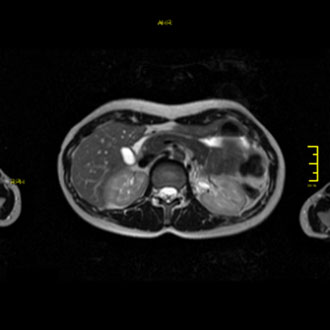

Die MRT des Pankreas ist die Methode der Wahl zur Beurteilung der Bauchspeicheldrüse.

Sie wird eingesetzt bei Verdacht auf Pankreastumoren, Zysten oder Entzündungen (Pankreatitis).

Im Kernspin Zentrum Köln ermöglicht die MRT eine präzise Abgrenzung des Pankreasgewebes und eine sichere Differenzierung zwischen akuten und chronischen Veränderungen – ganz ohne Strahlenbelastung.